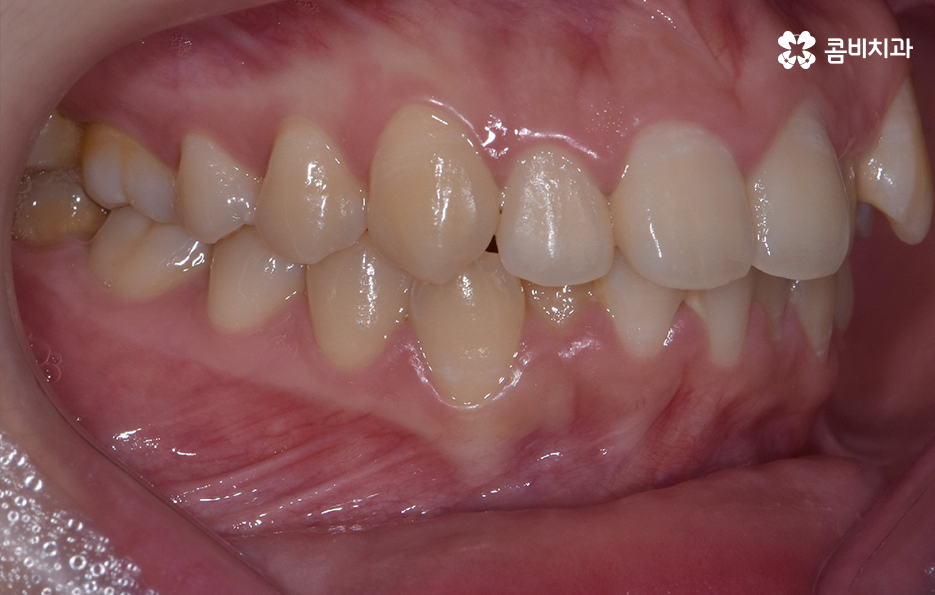

오늘 덧니 비발치 교정 사례로 보시는 환자분의 경우에는 윗니와 아랫니 앞니 부분에 조금씩 덧니가 있는 상태로 덧니를 제외하면 대체적으로 치열 상태는 고른 편이며 덧니 교정 사례 중에서는 돌출입도 함께 개선해야 하는 경우가 많지만 위 환자분의 경우에는 돌출입의 정도가 양호했고 입술라인 역시도 정상 범위에 가까웠기 때문에 발치를 필요로 하지 않았지만 치아의 이동 공간과 보다 자연스러운 입술라인 그리고 얼굴형과의 조화를 고려하여 악궁 확장과 어금니 후방 이동을 적절히 활용하여 교정 치료가 진행되었다고 볼 수 있어요

대부분의 발치 교정의 경우 작은 어금니를 발치하여 치아의 이동 공간을 확보하는 경우가 많다면 덧니 비발치 교정의 경우 발치교정 만큼은 아니더라도 치아를 이동 시킬 공간을 약간이라도 확보해야 하기 때문에 악궁 확장이나 치간삭제를 하는 경우가 있으며 어금니 후방 이동이 필요할 경우에는 사랑니 발치를 해야할 수 있어요